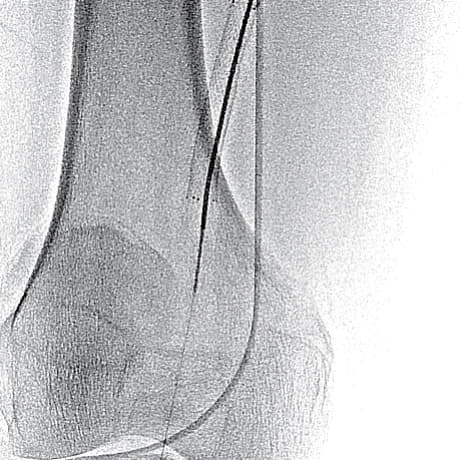

- マイクロカテーテルは硬化した閉塞部を通過せず、metal tip typeのマイクロカテーテルも通過しなかったことから、ブロッケンブロー針にて病変通過(図4)